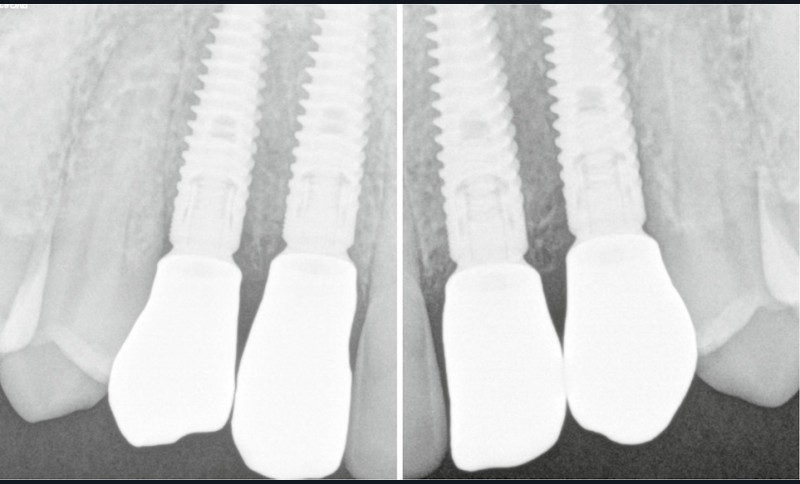

- mise en place de 4 implants Primetaper Dentsply (diamètre 3.6/ longueur 13 mm) ;

- vérification du positionnement implantaire et du torque à la clef dynamométrique : 45 Newton ;

- radiographies de contrôle (fig. 10b).